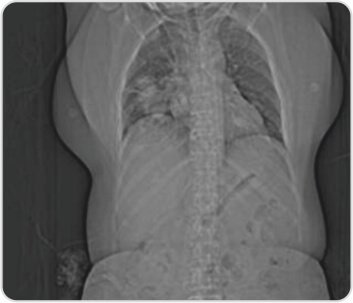

CT topogram of the chest reveals right lower lobe consolidation